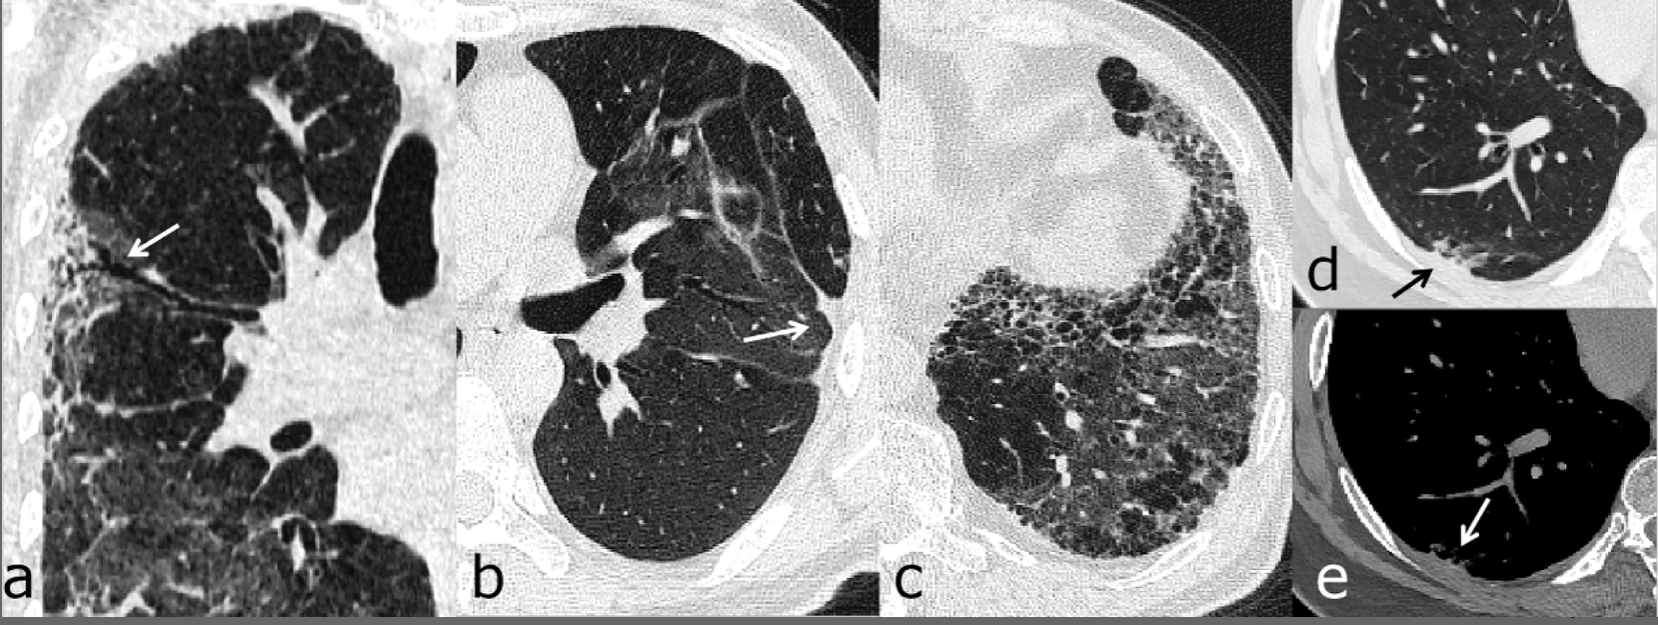

9/25 ct scan covid- In the early stage of the disease (Stage1), CT scans showed in 34 % lesions that involved a single lung lobe and in 212 % no lung involvement (Table 2) The most frequent CT findings of COVID19 pneumonia were GGO, crazypaving pattern, consolidation and linear opacities (Figs 1, 2) The predominant patterns of abnormality changed over timeGlobally, the accepted cutoff for Ct value for Covid19 ranges between 35 and 40, depending on instructions from the respective manufacturers of testing equipment The ICMR has arrived at the Ct value of 35 based on laboratory experiences and inputs taken from several virology labs

Notably — the method was initially suggested by M Chung et al (Radiology ) describing the CT findings of COVID19 and most popularly used by F Pan et al (Radiology ) on a study of the Lab testing for COVID19 (also known as the novel coronavirus or SARSCoV2) has increased greatly since the virus spread across the globe in spring Current evidence suggests that chest CT scans and xrays are generally NOT specific enough to either diagnose or rule out COVID19 on their own But imaging does have a limited role to play when used with lab tests, a Global data reveals that CT Chest for COVID19 has high sensitivity (>90%), high Negative Predictive Value (9596%),& good positive predictive value (65 %) CT shows abnormalities in 4050% of

Mean age 632 ± 158, range 27–90 years) with a positive RTPCR test for SARSCoV2 Apart from CORADS, HRCT scans also seldom mention CT severity score, which tells us about the actual lung involvement due to the infectionObjectives To correlate a CTbased semiquantitative score of pulmonary involvement in COVID19 pneumonia with clinical staging of disease and laboratory findings We also aimed to investigate whether CT findings may be predictive of patients' outcome Methods From March 6 to , 130 symptomatic SARSCoV2 patients were enrolled for this singlecenter analysis and